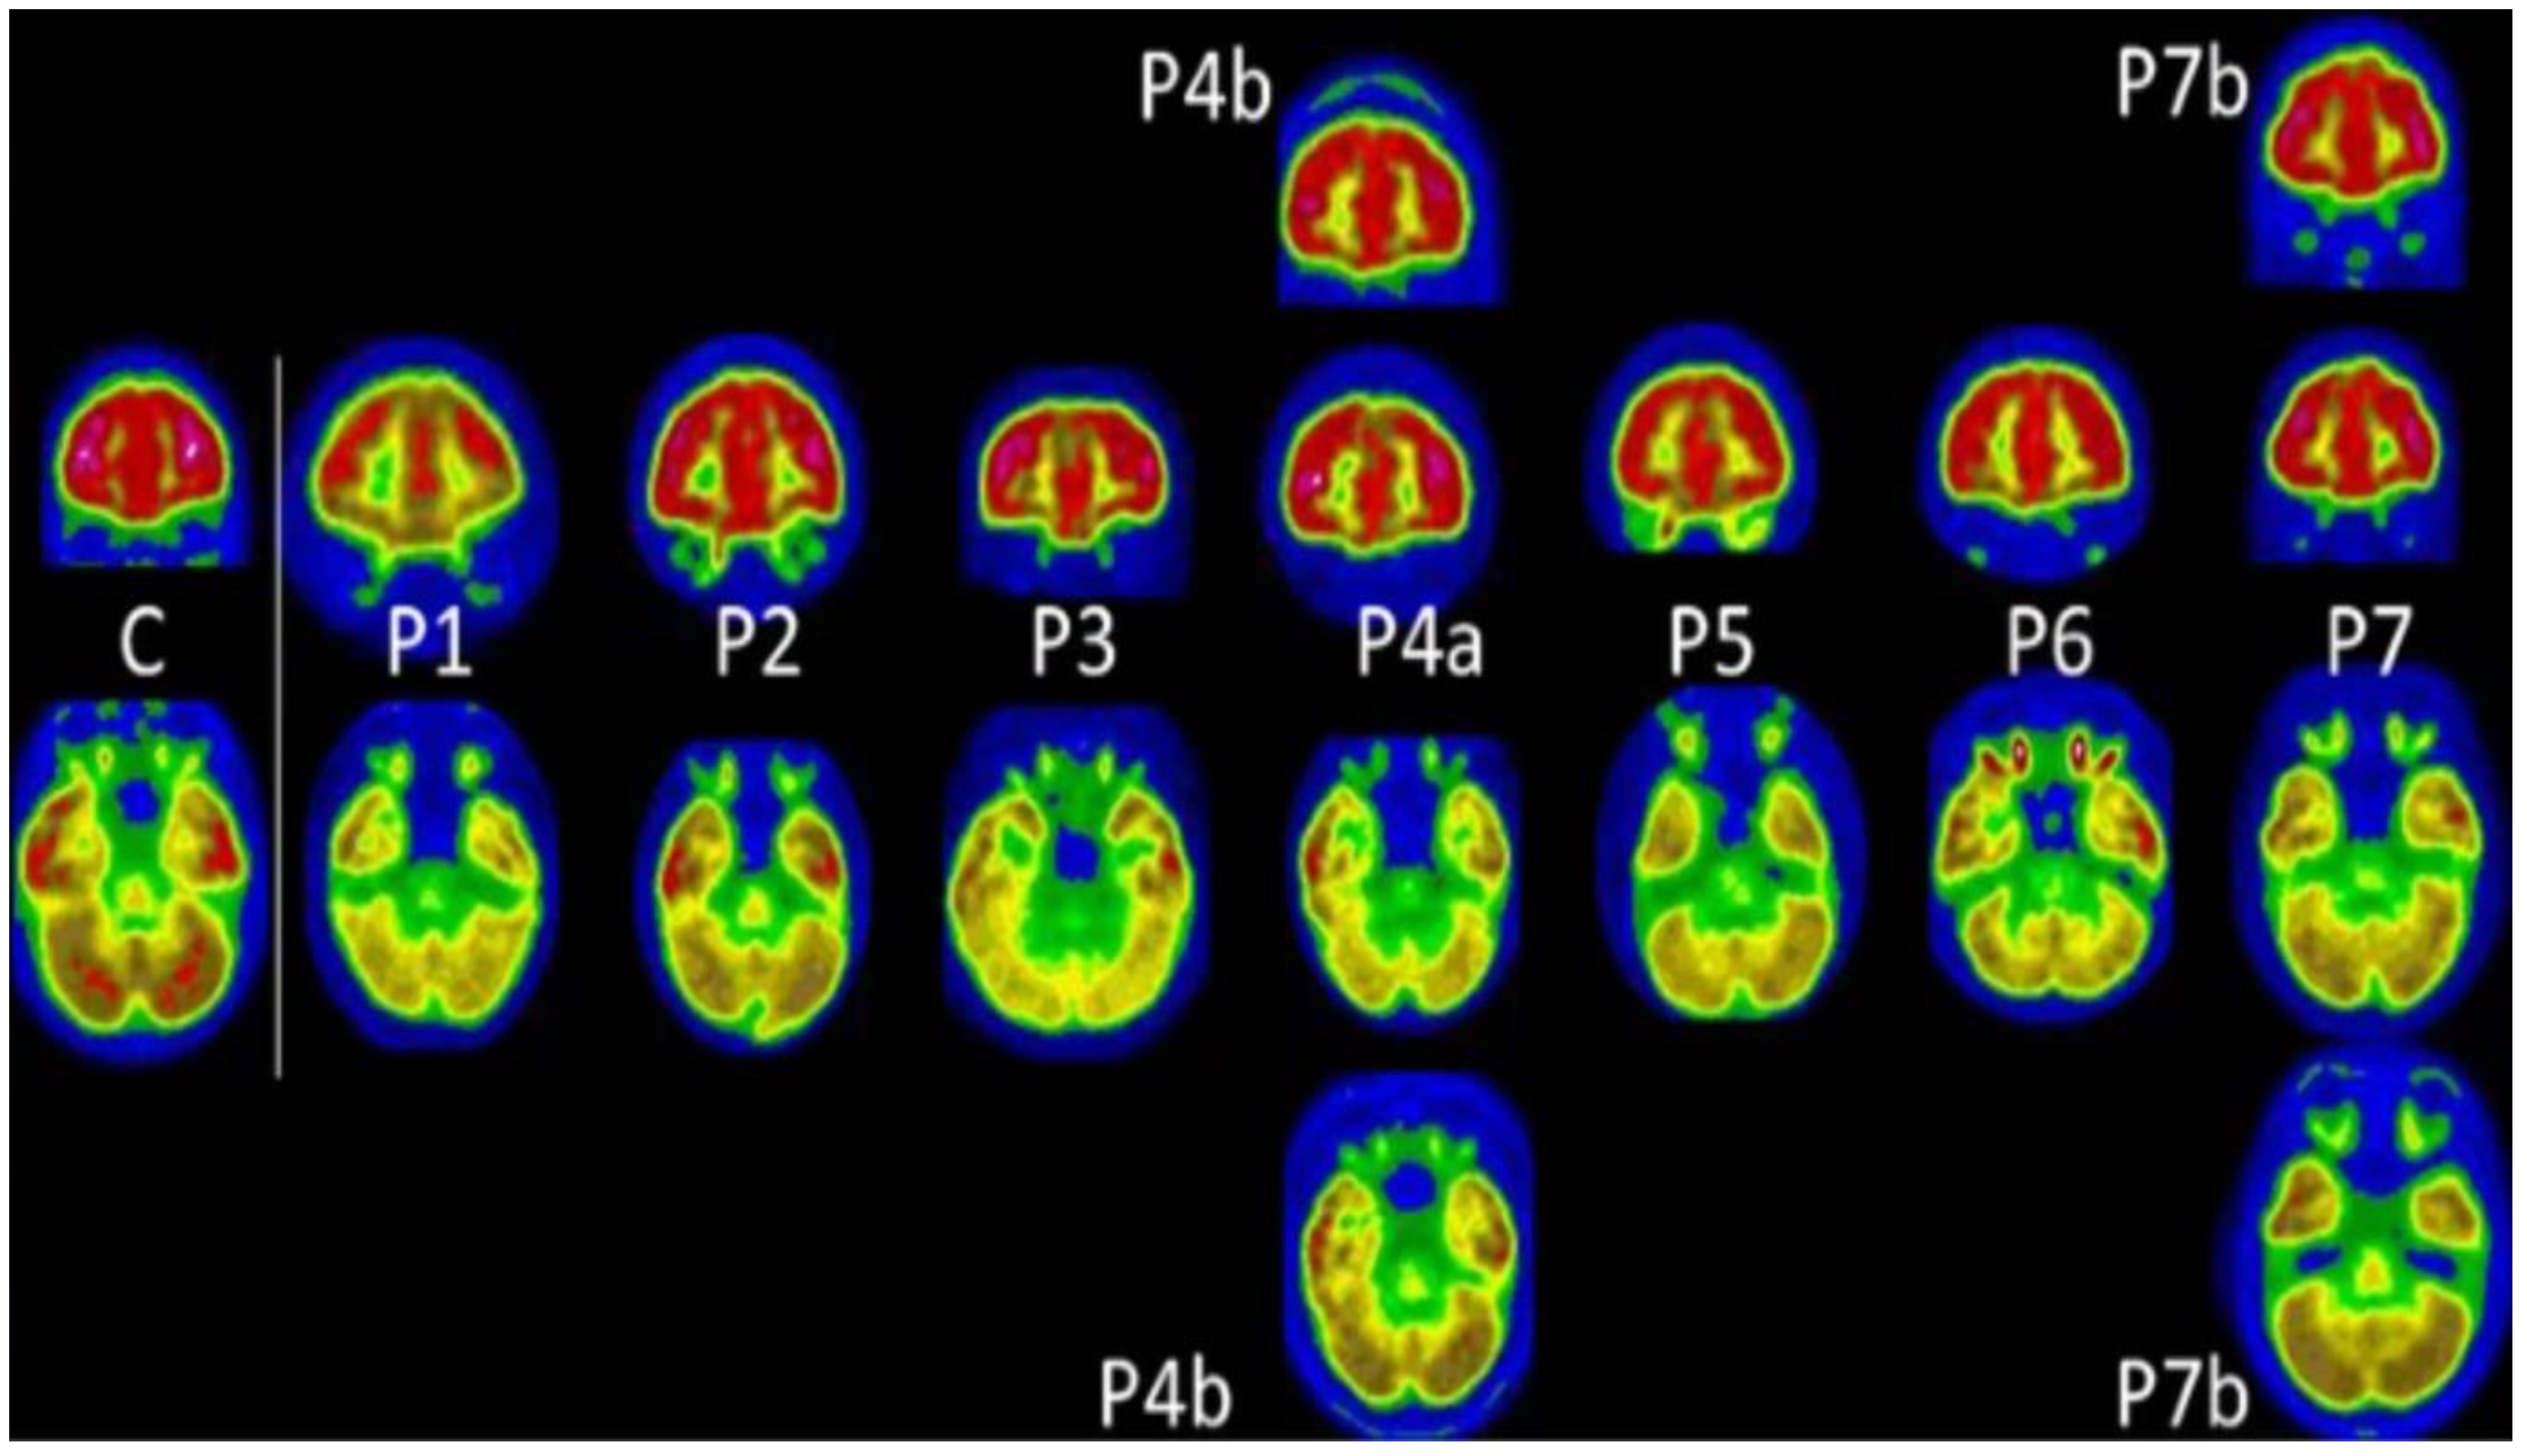

- Kas, A.; Soret, M.; Pyatigoskaya, N.; Habert, M.-O.; Hesters, A.; Le Guennec, L.; Paccoud, O.; Bombois, S.; Delorme, C. The Cerebral Network of COVID-19-Related Encephalopathy: A Longitudinal Voxel-Based 18F-FDG-PET Study. Eur. J. Nucl. Med. Mol. Imaging 2021, 48, 2543–2557. [Google Scholar] [CrossRef] [PubMed]

| Kas et al. [54] | Prefrontal, insular and subcortical | Cognitive and emotional disorders of varying severity remained with attention/executive disabilities and anxio-depressive symptoms | Approximately 6 months | Observational- prospective/7 subjects (4 males and 3 females; 2 had history of hospitalization) |